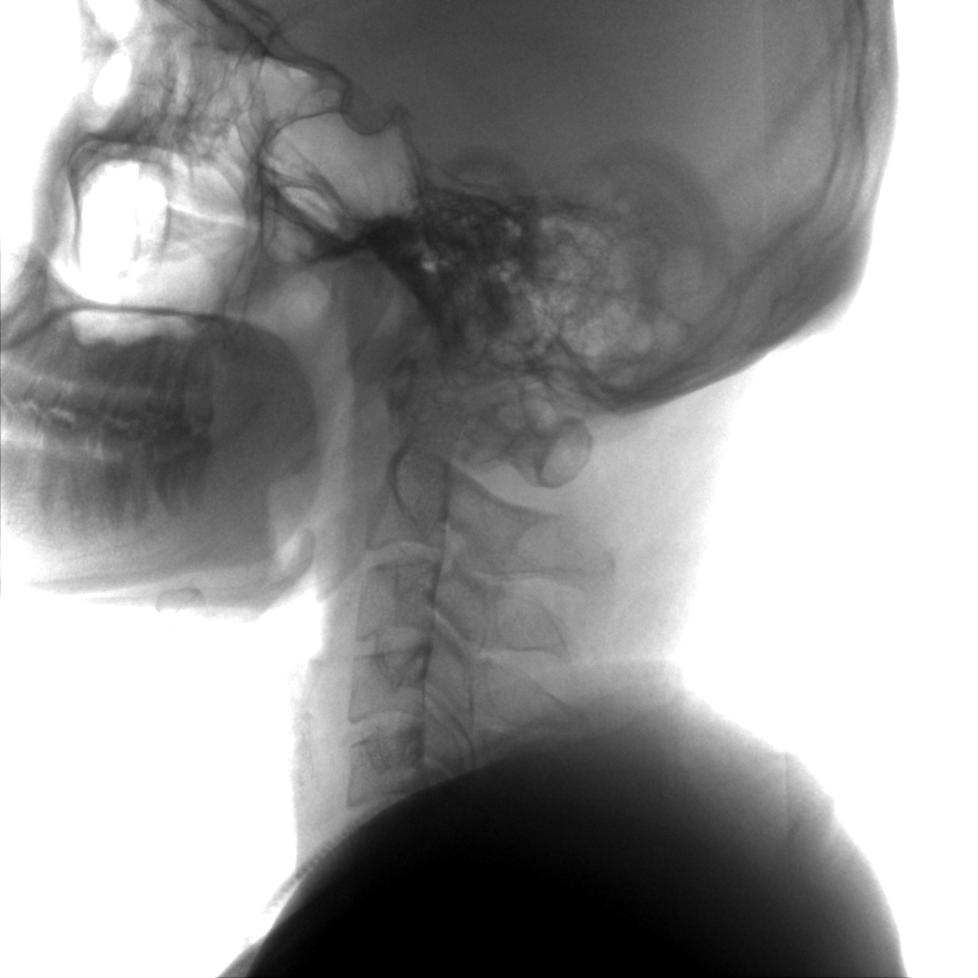

成像清晰、操作簡易、擺位便捷,主要適用于骨科、脊柱外科、矯形外科、創(chuàng)傷骨科及手術(shù)室等,能大幅度提升手術(shù)水準,降低手術(shù)風(fēng)險和并發(fā)癥的概率。

術(shù)中三維成像和橫斷面圖像提供多角度的手術(shù)診斷信息,輔助醫(yī)生進行術(shù)中評估判斷,諸如骨折復(fù)位情況和內(nèi)植入螺釘?shù)某叽绾臀恢?,輔助手術(shù)更好地完成。

提供更大的術(shù)中三維成像視野,采集更多圖像信息,可一次拍全全段頸椎、全段腰椎、七節(jié)胸椎、雙側(cè)骶髂關(guān)節(jié)、股骨頭及單側(cè)盆骨。